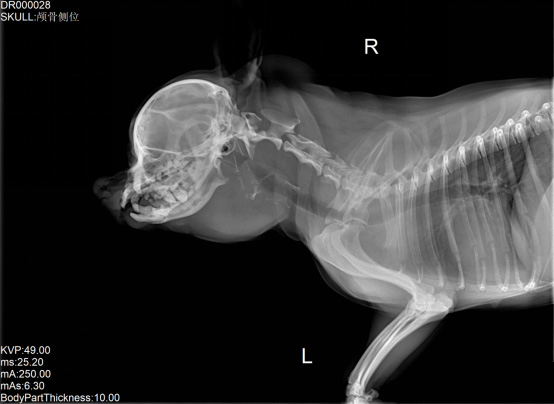

寵物DR是專業(yè)用于寵物X光拍攝的數(shù)字化X射線檢查,輔助寵物醫(yī)生進行及時精確的診療。寵物DR主要包括五大主要部件,數(shù)字X光探測器,高壓發(fā)生器,球管,機架,寵物專用的DR工作站軟件。寵物DR由于采用數(shù)字技術(shù),自動成像處理,模擬X線圖像向數(shù)字化X線圖像的轉(zhuǎn)變。寵物DR與傳統(tǒng)模擬X光機相比有什么優(yōu)勢呢?采集時間10毫秒以下,成像時間僅為3秒,較高的空間分辨力和低噪聲率,提高了病灶的檢出率,避免漏診誤診等問題。減少X線對人體照射的不良影響寵物DR照片是您最佳的選擇。提高寵物醫(yī)生工作效率,總而言之,選擇寵物DR是寵物醫(yī)院的最佳選擇。寵物醫(yī)學(xué)影像學(xué)實現(xiàn)全數(shù)字化和無膠片化升級發(fā)展提高技術(shù)水平。